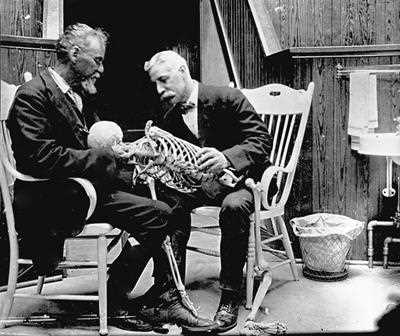

L’osteopatia nasce per merito del Dr. Andrew Taylor Styll (1828-1917) che visse tra il Kansas ed il Missuri. Styll fu un medico che si formò sul campo leggendo molti libri e studiando l’anatomia umana direttamente sui cadaveri degli indiani che lui stesso riesumava di nascosto. In seguito alla morte dei suoi tre figli per meningite e di una figlia per polmonite, intensificò i suoi studi a causa dell’insoddisfazione nei confronti della medicina tradizionale. Il suo principio si basava sul considerare il paziente malato nella sua totalità senza soffermarsi solamente sulla cura dei sintomi. Dopo una decina di anni presentò presso la Baker University, struttura che lui stesso contribuì a costruire, un suo primo lavoro sull’osteopatia che non venne assolutamente preso in considerazione (1874). La sua perseveranza, nonostante l’indifferenza del mondo medico, era premiata ed alimentata dal gradimento e dalla riconoscenza dei pazienti che aumentavano sempre di più attratti dal fatto che questo dottore curava senza l’utilizzo di farmaci. La prima scuola di osteopatia, l’American School of Osteopathy, fu ufficialmente fondata nel 1892 ed era composta da 21 allievi (uomini e donne) fra cui alcuni componenti della sua famiglia. Si cita che la vera e propria scoperta dell’osteopatia di Still fu alla tenera età di 10 anni e che fu casuale, quando, colpito da una forte emicrania, tese una corda tra due alberi e si appoggiò col capo come fosse un cuscino. Addormentatosi al suo risveglio il mal di testa era sparito, solo dopo anni di studi capì che la corda aveva inibito il funzionamento del nervo grande occipitale e permise un rilassamento totale del collo, aveva cioè sospeso l’attività dei grandi nervi occipitali, armonizzando il flusso del sangue arterioso. Aveva fatto dell’osteopatia!

Ad un certo punto della sua vita Still conobbe un uomo, tale John Martin Littlejohn.

John Martin nacque in Scozia nel 1865, uomo dall’intelletto fenomenale ma dalla salute cagionevole. Soffriva infatti di gravi emorragie alla gola tanto che un medico luminare dell’epoca gli consigliò di emigrare in paesi dai climi più caldi dandogli pochi mesi di vita. John Martin partì per l’America dove, sentendo parlare del Dr. Still, decise di farsi trattare non avendo nulla da perdere. Guarì completamente e decise di intraprenderne gli studi osteopatici divenendo discepolo diretto del Dr. Still. Entrambi si dedicarono alla ricerca, facendo diversi esperimenti e perfezionando sempre di più l’arte di guarire con le mani.